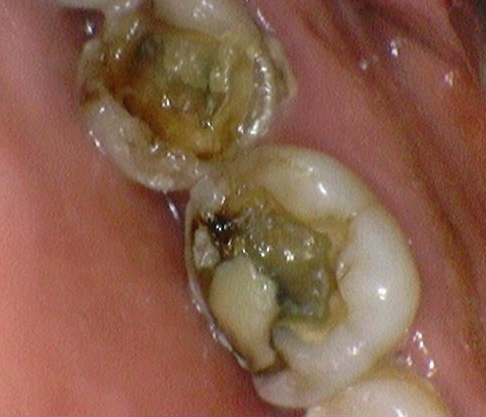

원래는 이렇게 예전에 다른 치과에서 떼워놓으신 인레이가 떨어지고

치아가 많이 깨져있는 상태였습니다.

더 깨지거나 시리지 않기 위해 크라운을 씌워서 보호해주었습니다.

전후 사진